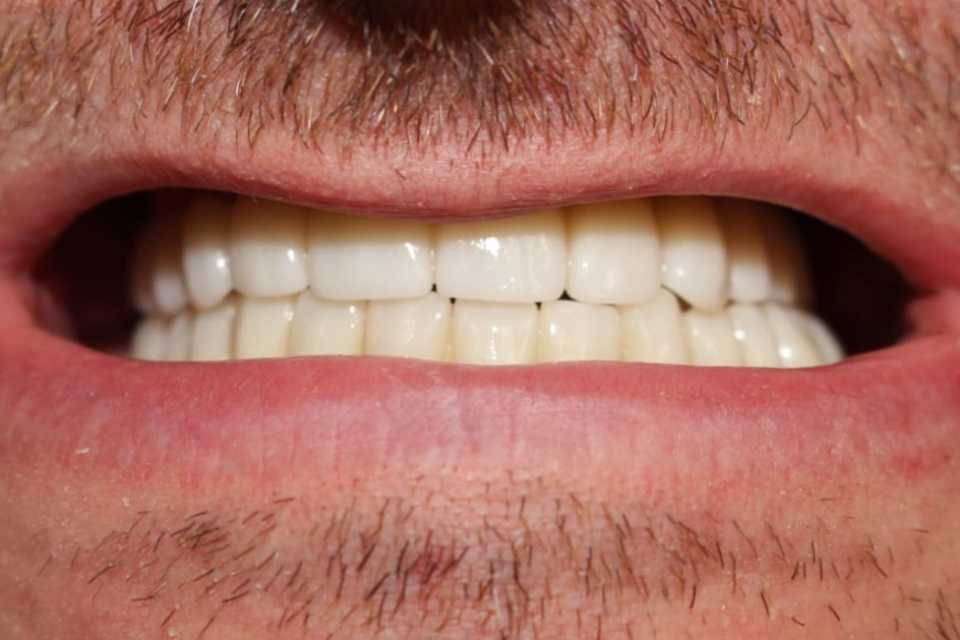

Pacient în vârstă de 41 de ani, purtător de proteze dentare mobile de aproximativ 5 ani, cu resorbții osoase severe la nivelul maxilarului și al mandibulei, s-a prezentat în cadrul clinicii noastre cu dorința reabilitării orale fixe cu ajutorul implanturilor dentare.

Cazul a fost o adevărată provocare, nu numai chirurgical, dar și protetic. Prin prisma resorbției osoase severe maxilare în zona frontală și a purtării îndelungate a protezelor mobile, la momentul consultului inițial, pacientul prezenta un etaj inferior al feței micșorat cu profil concav .

Reabilitarea orala funcțională și estetică, s-a realizat cu ajutorul unei lucrări fixe cimentate la nivelul maxilarului din ceramica pe zirconiu și a 3 lucrări din ceramica pe zirconiu fixe cimentate la nivelul mandibulei.